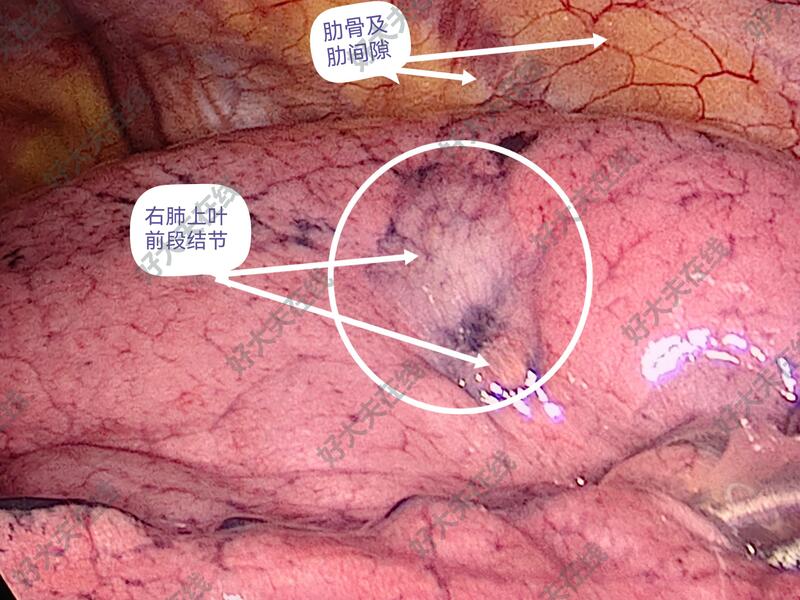

图1-5,女性,45岁,体检发现右肺上叶前段结节,亚实性(磨玻璃)结节、毛刺、分叶、胸膜牵拉等,短期随访结节不消散。胸腔镜微创手术切除,病理报告为肺浸润性腺癌。

治疗中

均胸腔镜微创手术切除,并送病理检查,已经出具病理报告,拔出胸腔闭式引流管,出院。并复查胸片。